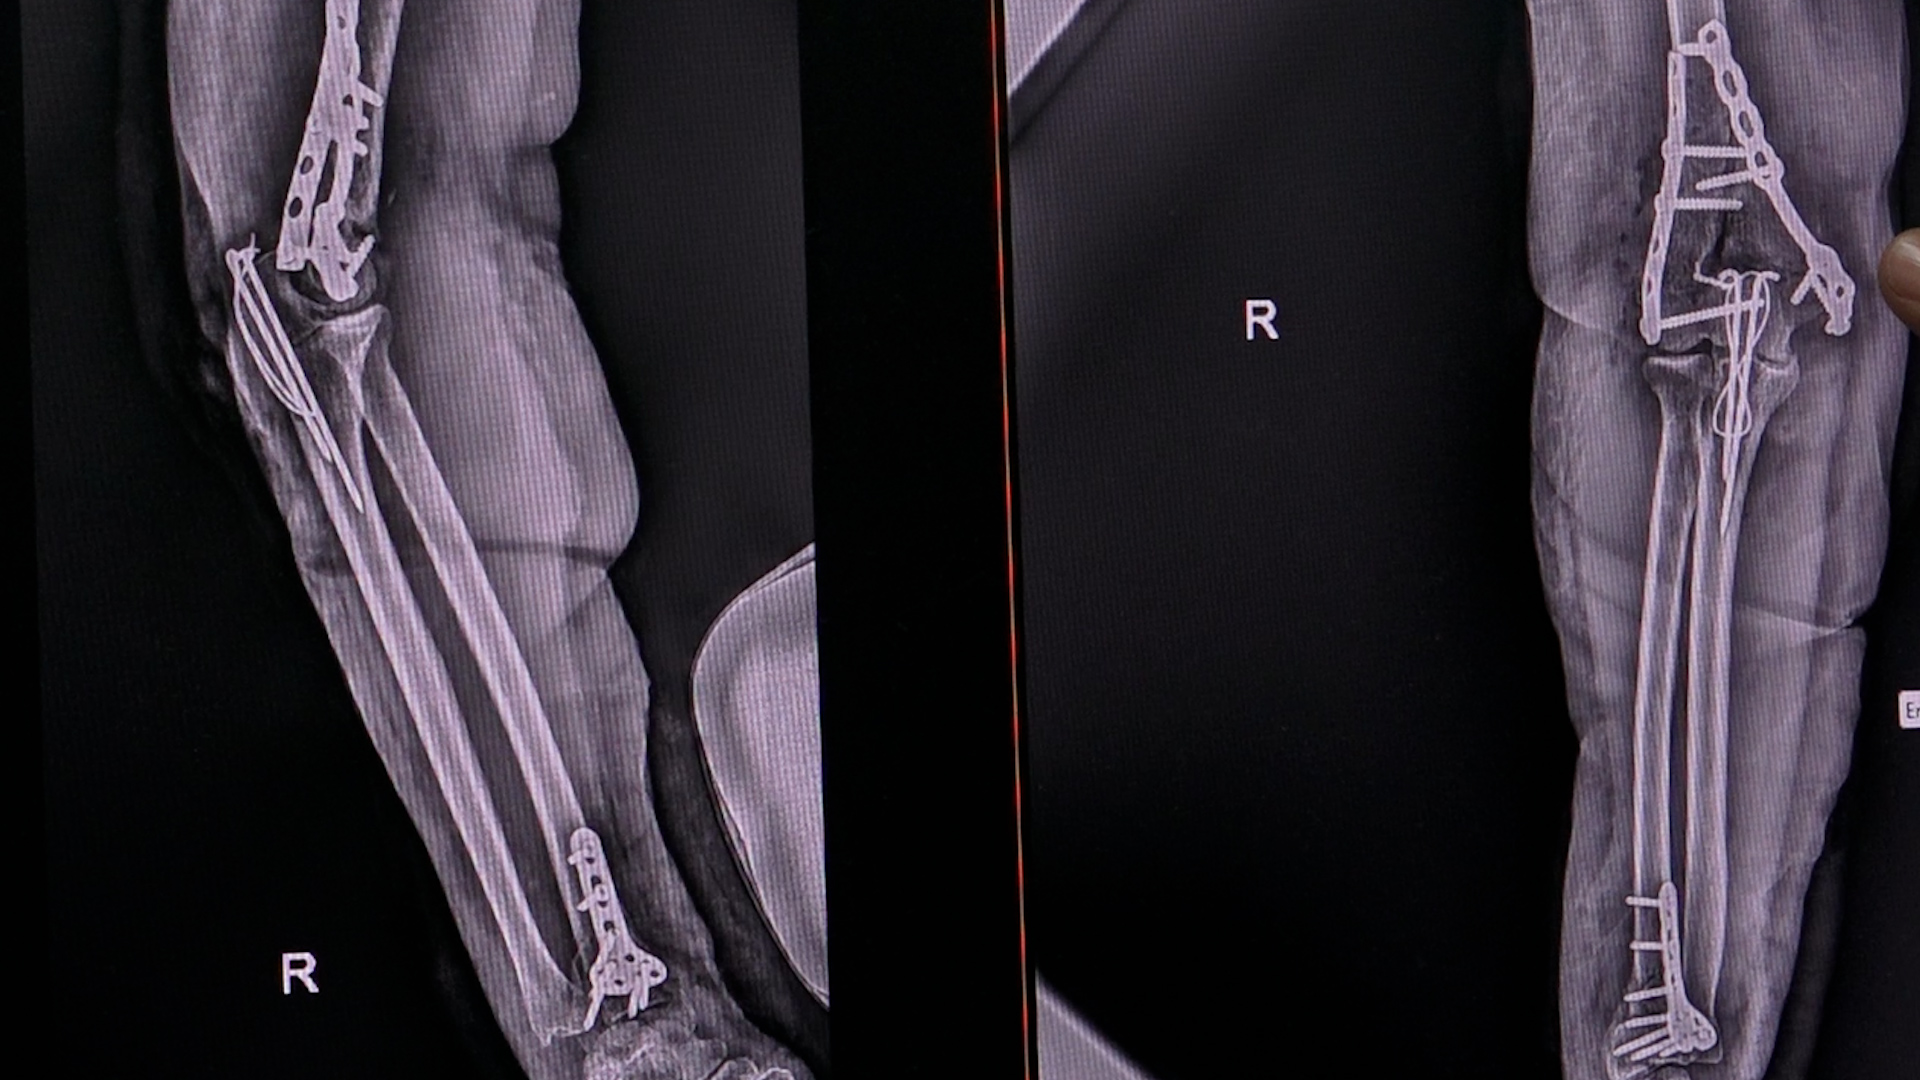

Povećanje broja ljudi koji imaju prelome u prethodnim ledenim danima povećan je u Urgentnom centru. Na ortopediji je primljeno više pacijenata kojima je potrebno hitno medicinsko zbrinjavanje i operacija. Lekari apeluju sugrađanima da ne izlaze bez potrebe, dok je klizavo i poledica.